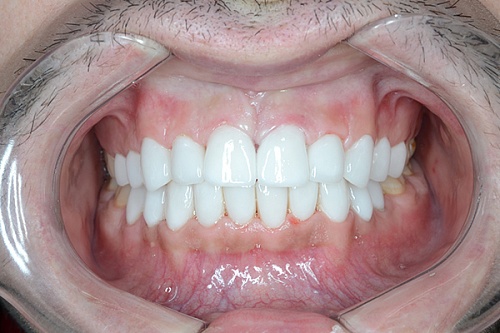

Изменения тканей, которые окружают корни зубов, к сожалению, неизбежны и с возрастом наблюдаются у всех, однако в разном объеме. Так, на развитие пародонтита влияет болезнетворная микрофлора полости рта, которая есть у каждого из нас, но на мы в силах повлиять на ее количество.

Сохранить зубы и пародонт помогает правильная гигиена полости рта дома и в кресле стоматолога, а также своевременное протезирование и имплантация, которые замещают удаленные зубы и равномерно распределяют жевательную нагрузку, не позволяя костной ткани атрофироваться.

Таким образом, по мнению стоматологов, риск возникновения болезней десен на 80% зависит от сознательности самого пациента.